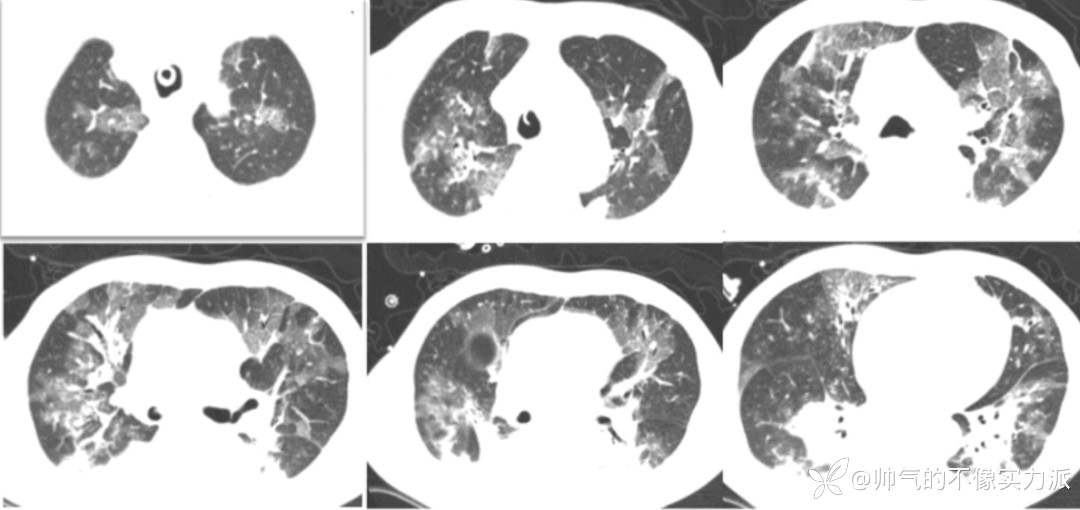

急诊胸部CT

2020年12月7日,急诊胸部CT提示肺部慢性炎症,右肺小结节影(图1)。

图1 患者胸部CT(2020-12-07)